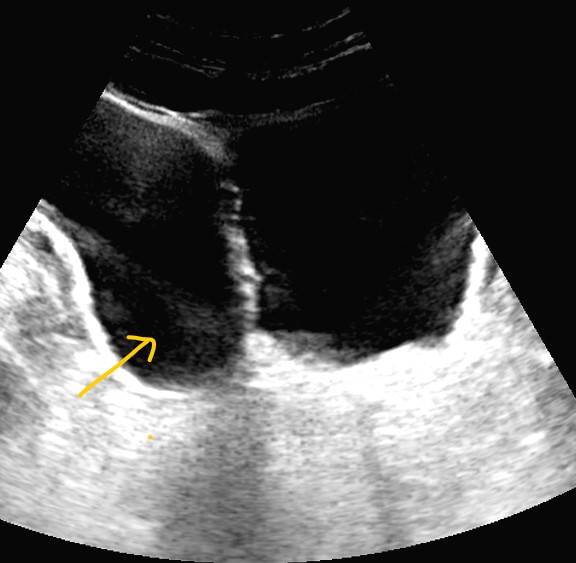

Riñones de tamaño y morfología normales. No observamos litiasis ni dilatación de la vía urinaria. A nivel de la vejiga presenta un tabique con comunicación a una gran cavidad en la pared lateral derecha que da la impresión de que existen dos vejigas urinarias. No hay lesiones parietales. Próstata 32 cc. Volumen premiccional de la cavidad mayor 350 cc y posmiccional 210 cc.

Gran divertículo de vejiga urinaria.

Vejiga urinaria con presencia de jets ureterales, de paredes lisas con un gran divertículo en la pared lateral derecha de 543 cc premiccional que vacía a la mitad en posmiccional 310cc (57%).Volumen vesical premiccional 620cc y posmiccional 179 cc (28%).